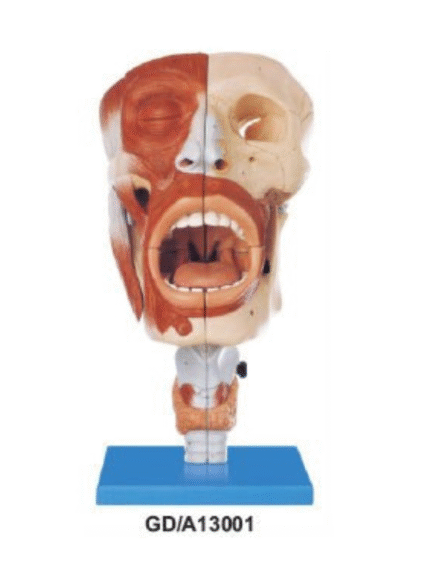

ATL-131 HALF MUSCULAR HEAD WITH VESSEL SOFT